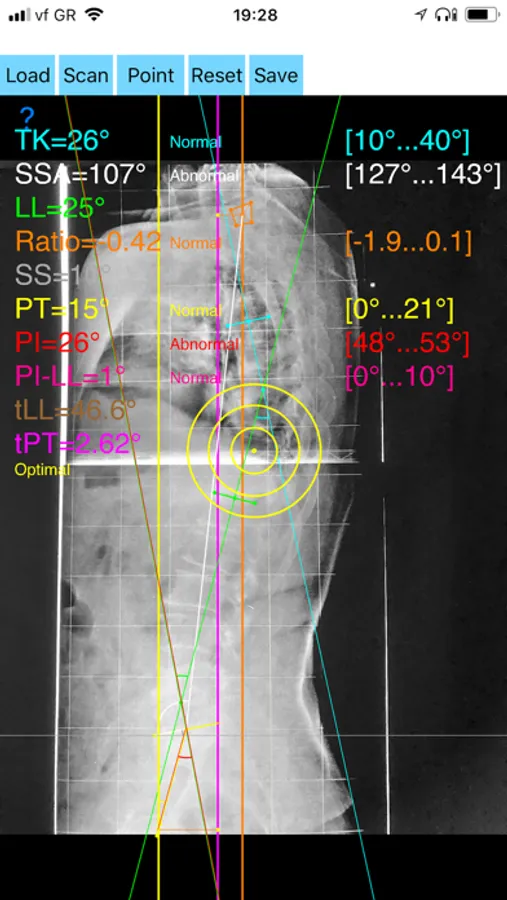

-By marking several points at the image of X-ray, the App calculates and offers a very convenient way to determine the most accurate possibly way at once, Pelvic incidence (PI), Sacral slope (SS), Pelvic Tilt (PT), Lumbar lordosis (LL), thoracic kyphosis, C7 plumb line (C7PL), C7PLD/sfd ratio, PI–LL, theoretical normal pelvic tilt (tPT),theoretical normal L1-S1 lumbar lordosis (tL1S1), Spino-sacral angle (SSA) According to measured parameters the app categorizes the severity of the imbalance of spine, in three different stages: optimal balanced, balanced with compensatory mechanisms and imbalanced.

-The app also allows the calculations of centroids after choosing points in vertebra body in independent manner from order.